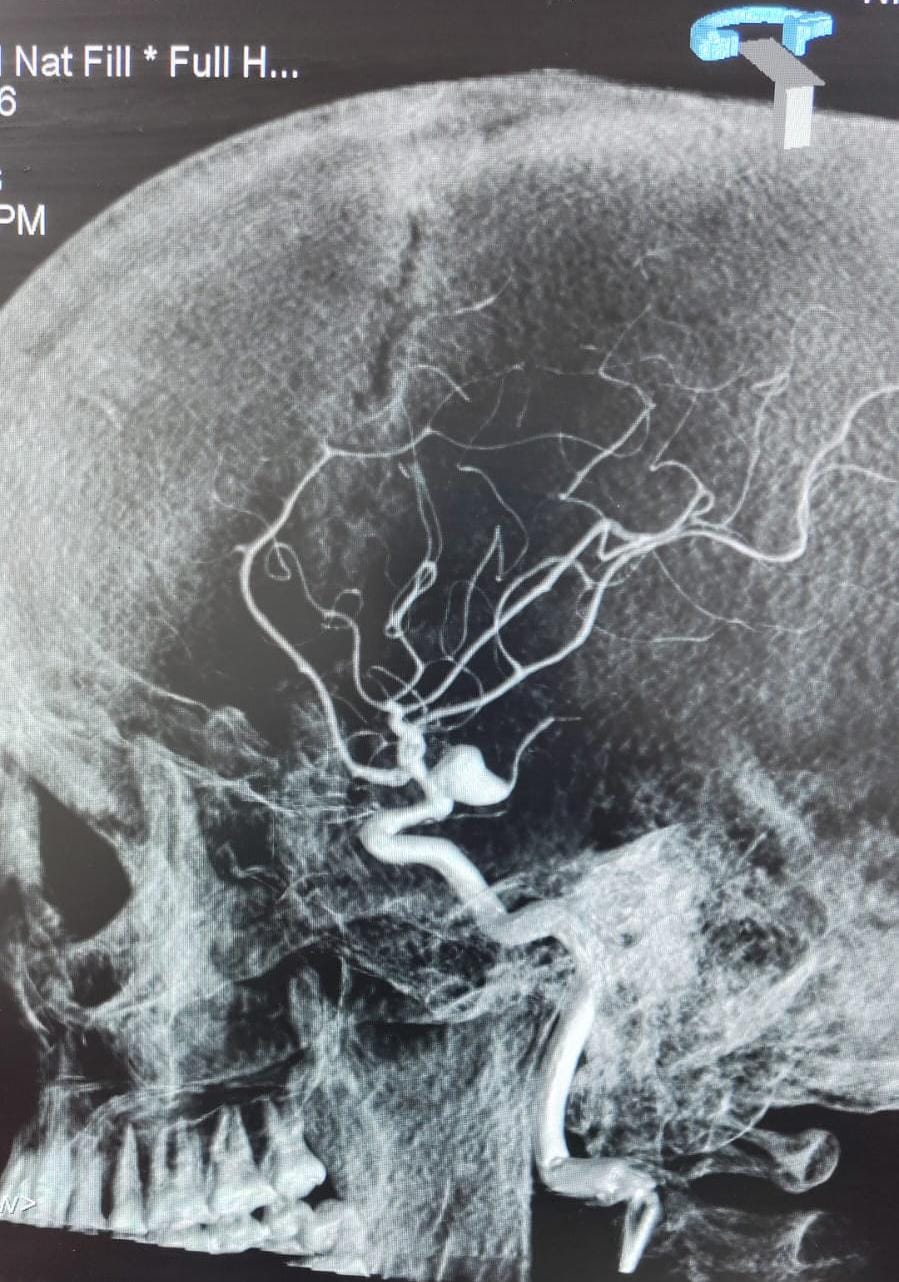

Ruptured Brain aneurysm (left ICA communicating segment wideneck aneurysm) treated with Stent Assisted Coiling.

final result complete coiling and Stenting of brain aneurysm